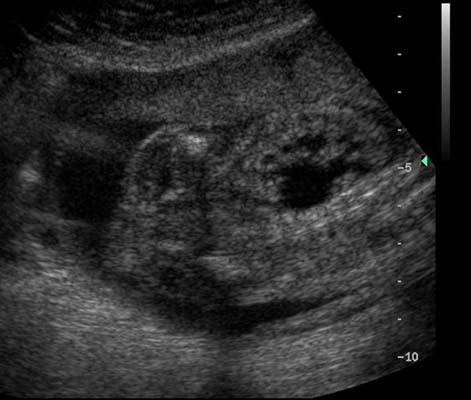

Anéchogène ovalaire